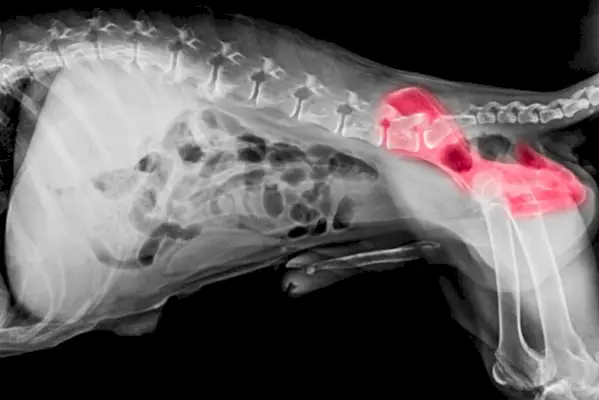

2. Magendilatation und Volvulus

Dies ist eine ernste Erkrankung, die tödlich sein kann. Es kommt relativ häufig vor und wird manchmal als Magendrehung oder Blähungen bezeichnet. Airedales sind aufgrund ihrer Größe und Statur dafür anfällig – sie haben eine tiefe, schmale Brust, die diese Erkrankung begünstigt. Der Magen kann sich um seine Achse drehen und sich schnell mit Gas füllen. Durch die Magendrehung wird die Blutversorgung des Magens und der Milz beeinträchtigt. Unbehandelt kann die Erkrankung sehr schnell zum Tod führen.

Zu den klinischen Anzeichen einer Magendilatation und eines Volvulus gehören:- Großer, aufgeblähter Bauch

- Hypersalivation

- Unproduktives Würgen

- Blasses Zahnfleisch

- Die Gebetsposition einnehmen

- Tempo/Unruhe

- Zusammenbruch

Blähungen können auch alleine auftreten. Dies geschieht, wenn sich der Magen des Hundes mit Feststoffen (Futter), Flüssigkeiten oder Gas füllt, wodurch er sich ausdehnt und großen Druck auf andere Organe in der Nähe des Magens ausübt. Es kann ganz plötzlich passieren.

Wenn Sie den Verdacht haben, dass Ihr Hund eine Magendrehung oder Blähungen haben könnte, suchen Sie sofort einen Tierarzt auf. Die Behandlung umfasst die Stabilisierung des Herz-Kreislauf-Schocks, eine aggressive Flüssigkeitstherapie und die Schmerzlinderung bei der Vorstellung. Ihr Tierarzt wird dann versuchen, eine Magensonde einzuführen, um den Magen nach Möglichkeit zu entlasten. Wenn der Patient stabil genug für eine Operation ist, ist eine Notfalloperation erforderlich, um den Magen zu entdrehen und Magen und Milz wieder in ihre richtige Position zu bringen. Manchmal müssen Teile der Magenwand und der Milz entfernt werden, wenn Schäden aufgetreten sind. Um zu verhindern, dass sich der Magen erneut verdreht, kann eine Gastropexie durchgeführt werden.